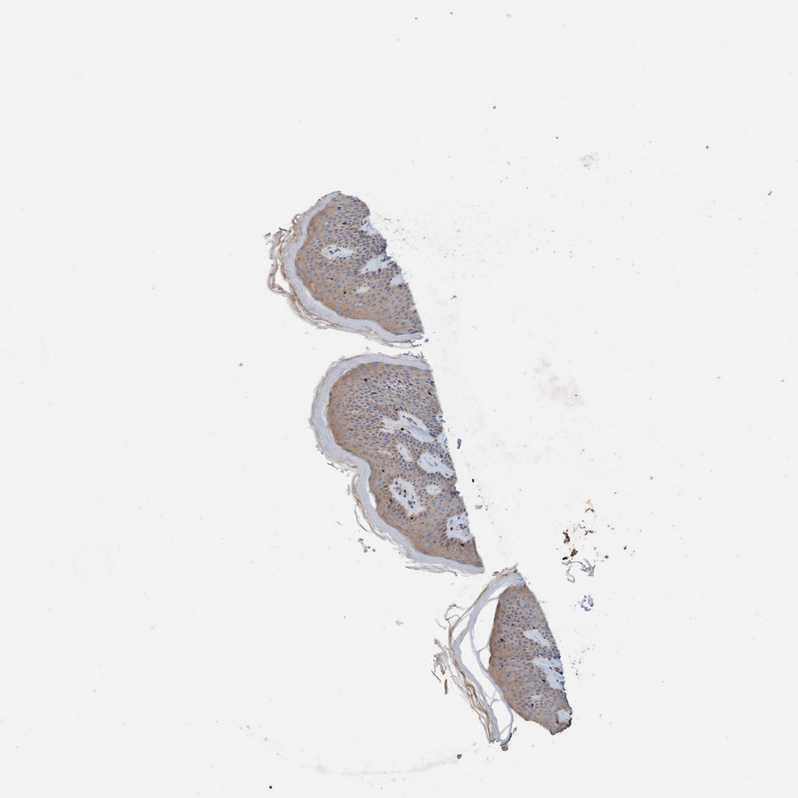

SKIN 1 - Antibody stainingi

Antibody staining in the annotated cell types in the current human tissue is reported as not detected, low, medium, or high, based on conventional immunohistochemistry profiling in selected tissues. This score is based on the combination of the staining intensity and fraction of stained cells.

Each image is clickable and will lead to virtual microscopy that enables deeper exploration of all samples and also displays staining intensity scores, fraction scores and subcellular localization as well as patient and tissue information for each sample.

Antibody HPA023584Antibody HPA024814

Langerhans HighNot detected

Fibroblasts MediumLow

Keratinocytes MediumLow

Melanocytes MediumNot detected

SKIN 2 - Antibody stainingi

Epidermal cells MediumMedium